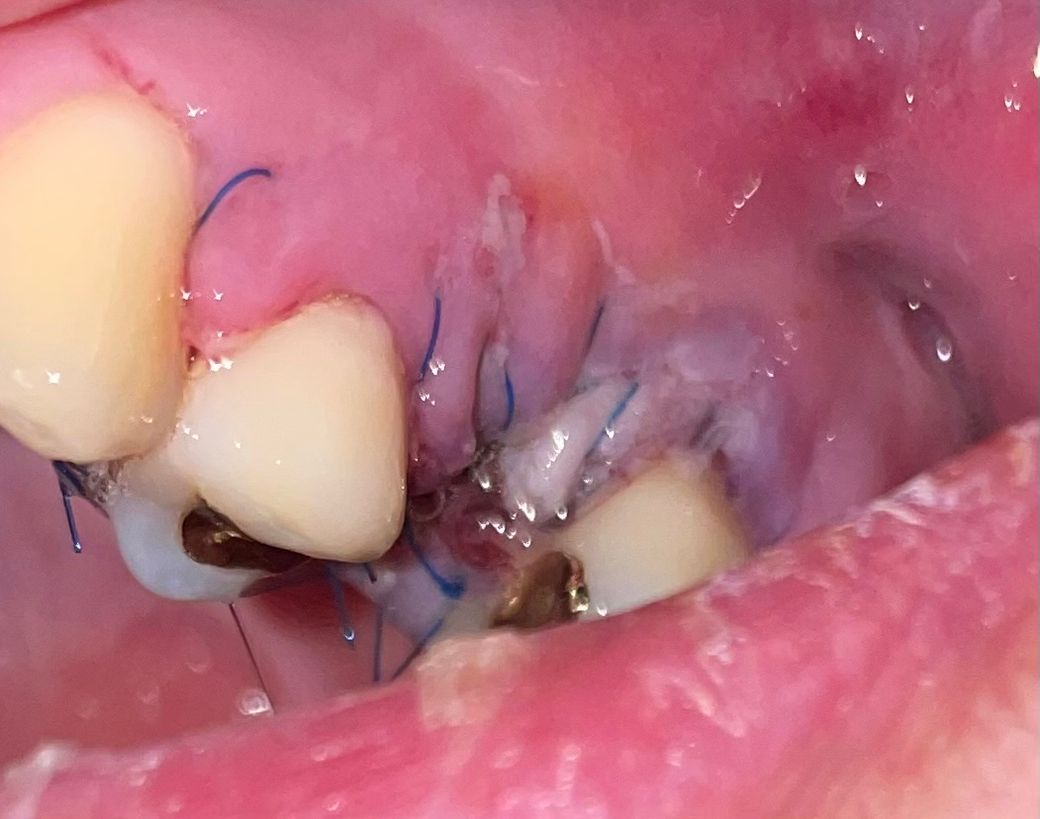

어제 상악동 거상술을 받았습니다 뼈 이식 까지 해였는데 실밥이 혀를 너무 찌르고 쓸려서 혀가 너무 아파서 수술부위 사진을 찍어보니 잇몸이 터진듯한 하얀 무언가도 보이고 잘못 ㄷ된건가요?

안녕하세요 치과의사 김철진입니다. 실밥때문에 찔리는거고 크게 문제가 잇거나 그렇진 않습니다. 잘 치유되고 잇는상태이니 너무 걱정하지 않으셔도 됩니다.

• 상학동 거상술은 수술 범위가 상대적으로 높은 술식입니다. 이런 잇몸 수술을 하게 되면 잇몸에 상처가 생기게 되고 아무는 과정에서 가피 등이 형성될 수 있습니다. 사진으로 보였을 경우에는 크게 문제가 없을 것으로 보이나 자세한 확인을 위해서 코에서 진료를 받아보는 것을 권유드립니다.

• 사진상 잘못되어 보이는 부분은 없습니다. 뼈이식 후에는 차폐막으로 닫아놓아서 하얗게 보이는 것이 맞습니다.

붓기가 심하거나 통증이 심하면 치과 가보시는 게 좋습니다.